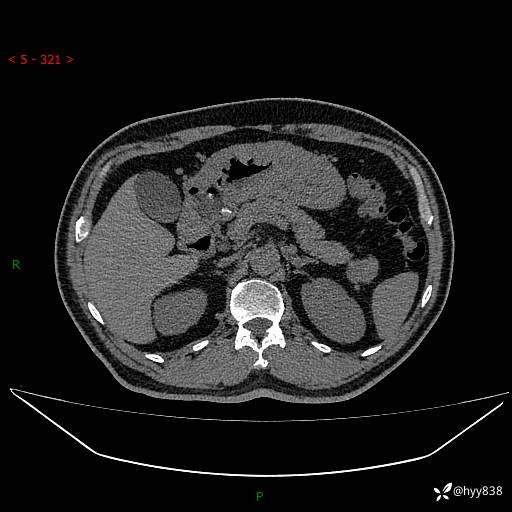

静脉期